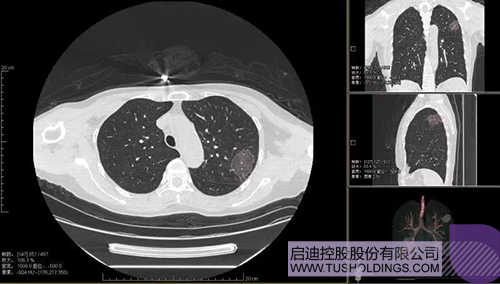

2020年2月11日,啟迪科服投資企業(yè)—神州德信推出新冠肺炎檢測及量化智能分析系統(tǒng),積極助力一線醫(yī)務人員科學精準防疫。

2020年3月4日,繼由啟迪之星和啟迪裕麟?yún)⑴c投資的產(chǎn)學研一體化項目被《新聞聯(lián)播》報道后,由啟迪科服投資企業(yè)與西安交大聯(lián)合研發(fā)的新冠肺炎AI數(shù)字診斷技術亦被《新聞聯(lián)播》報道。